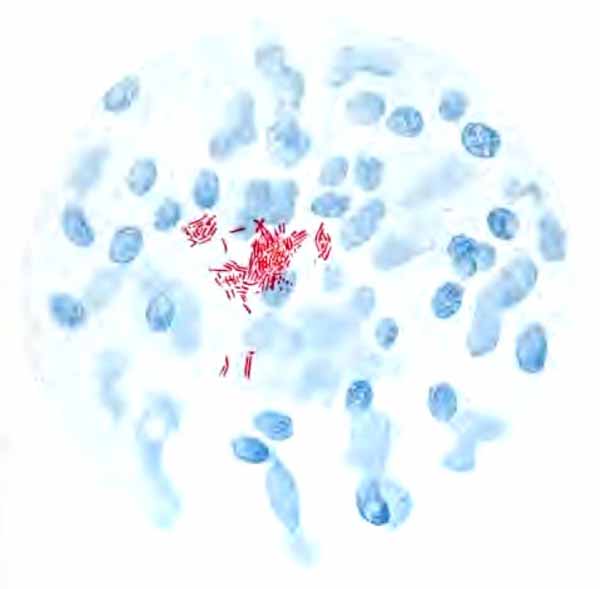

(1) Tubercle Bacillus.—The presence of the tubercle bacillus may be taken as positive evidence of the existence of tuberculosis somewhere along the respiratory tract, most likely in the lung. In laryngeal tuberculosis they are not easily found in the sputum, but can nearly always be detected in swabs made directly from the larynx.

Recognition of the tubercle bacillus depends upon the fact that it stains with difficulty; but that when once stained, it retains the stain tenaciously, even when treated with a mineral acid, which quickly removes the stain from other bacteria. The most convenient method for general purposes is here given in detail:

In films stained by Gabbet's method tubercle bacilli, if present, will be seen as slender red rods upon a blue background of mucus and cells (Plate II, Fig. 2). They average 3 to 4 µ in length—about one-half the diameter of a red blood-corpuscle. Beginners must be warned against mistaking the edges of cells, or particles which have retained the red stain, for bacilli. The appearance of the bacilli is almost always typical, and if there seems room for doubt, the structure in question is probably not a tubercle bacillus. They may lie singly or in groups. They are very frequently bent and often have a beaded appearance. It is possible that the larger, beaded bacilli indicate a less active tuberculous process than do the smaller, uniformly stained ones. Sometimes they are present in great numbers—thousands in a field of the one-twelfth objective. Sometimes several cover-glasses must be examined to find a single bacillus. At times they are so few that none are found in stained smears, and special methods are required to detect them. The number may bear some relation to the severity of the disease, but this relation is by no means constant. The mucoid sputum from an incipient case sometimes contains great numbers, while sputum from large tuberculous cavities at times contains very few. Failure to find them is not conclusive, though their absence is much more significant when the sputum is purulent than when it is mucoid.

Their recognition depends upon the facts that they are extremely small bacilli; that most of them lie within the pus-cells; that their ends stain more deeply than their centers, sometimes giving the appearance of minute diplococci; and that they are decolorized by Gram's method of staining (Fig. 11).

Bacillus of influenza

FIG. 11.—Bacillus of influenza; cover-glass preparation of sputum from a case of influenza, showing the bacilli in leukocytes; highly magnified (Pfeiffer).